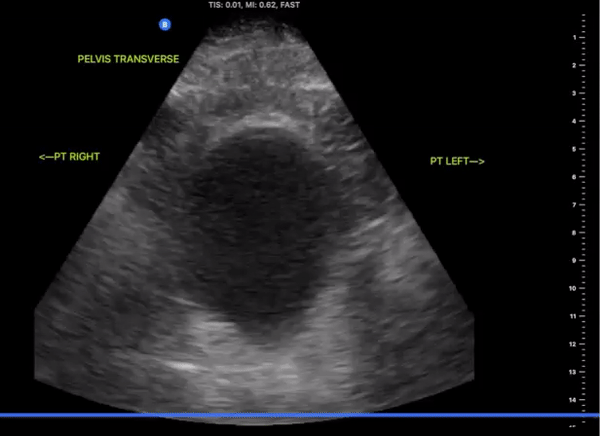

Pelvic Views

Probe/Preset:

Curvilinear / FAST, Abdominal, Bladder

Body Plane:

Transverse and Sagittal

​

Probe Indicator:

-

Transverse: Towards Patient’s Right

Sagittal: Towards Head

Depth:

At least 15cm

Location:

Patient Midline Superior to the pubic symphysis

Identify:

Bladder

Prostate (male)

Uterus/Uterine Stripe (female)

Notes:

Scan through the entire area assessing for the presents of free fluid. The bladder may be difficult to visualize if empty of urine. Small amounts of free fluid in pregnant females are a normal variant.